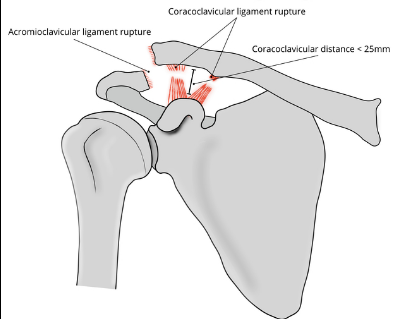

Based off Rockwood classification of acromioclavicular joint injury, what grade would this be?

3